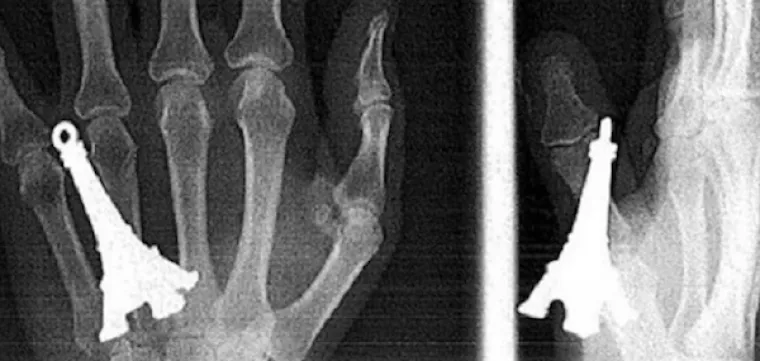

LJUDI SU ČAROBNO SPREMIŠTE, U NJIH STANE BAŠ SVE: Nevjerojatne snimke pokazuju što su sve uspjeli ugurati u sebe